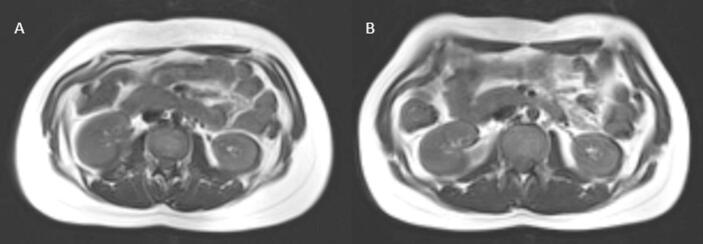

Conducted at the Medical University of Vienna between 2019 and 2022, the study included 15 TW and 20 TM. We conducted magnetic resonance imaging and spectroscopy to determine the visceral (VAT) and subcutaneous adipose tissue (SAT) amounts, the VAT/SAT ratio, and the intraorgan lipid content (liver, pancreas, myocardium), bloodwork, and an oral glucose tolerance test at baseline and after 6 months of GAHT.

Abstract Image